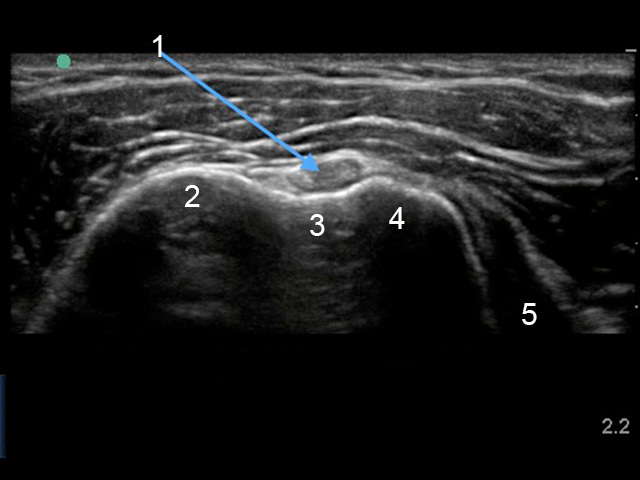

Shoulder Biceps Tendon Transverse Image

1. Long Head of the Biceps Tendon

2. Greater Tuberosity

3. Bicipital Groove

4. Lesser Tuberosity

5. Subscapularis Tendon